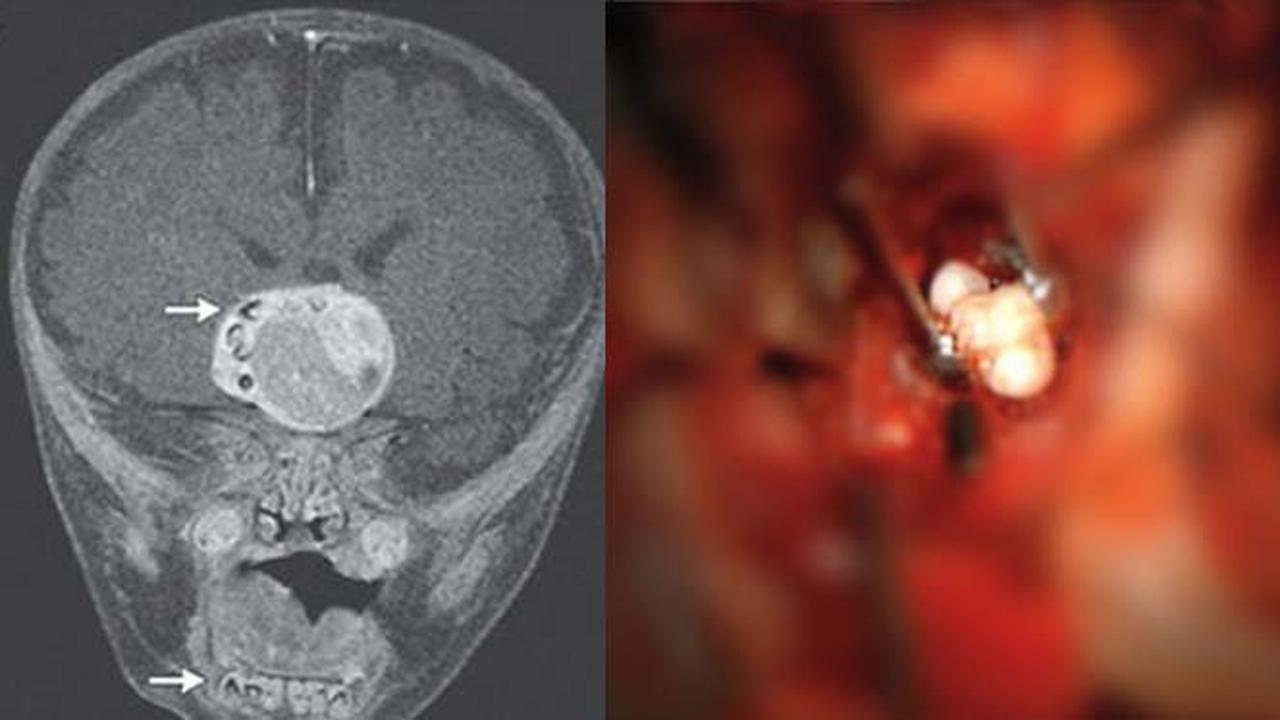

Dari hasil scan, di otak bayi laki-laki itu ditemukan sesuatu yang mirip gigi seperti di rahang bawah. Temuan medis yang jarang ini dilaporkan dalam New England Journal of Medicine edisi 27 Februari.

Dokter meminta bayi itu diperiksa MRI ketika mencurigai ada yang salah karena kepala anak tersebut tumbuh lebih cepat dibanding anak-anak lain. Dan hasil pemeriksaan menunjukkan ada tumor besar berisi sesuatu yang tampak seperti beberapa gigi yang sudah terbentuk sempurna.

Dokter mengatakan, tumor yang dimiliki bayi itu adalah craniopharyngioma yang tumbuh lambat sebesar bola golf tapi tak menyebar. Peneliti menduga tumor ini terbentuk dari sel-sel yang sama terlibat dalam pembuatan gigi, tapi sampai sekarang dokter belum pernah melihat gigi yang sebenarnya di dalam tumor.

Dokter mengambil gigi dan tumor dari kepala anak itu selama operasi otak. "Tidak setiap hari Anda melihat gigi di setiap jenis tumor di otak. Dalam craniopharyngiomas, ini jarang terjadi," kata Ahli Bedah Saraf Dr Narlin Beaty, yang melakukan operasi dan rekannya Dr Edward Ahn kepada Livescince, Jumat (28/2/2014).

Craniopharyngiomas umumnya mengandung endapan kalsium. Gigi telah ditemukan di otak manusia sebelumnya, tapi itu hanya pada tumor yang dikenal sebagai teratoma, yang unik di antara tumor karena mengandung tiga jenis jaringan yang ditemukan dalam embrio manusia. Sebaliknya, craniopharyngiomas hanya memiliki satu lapisan jaringan.

"Kasus anak itu memberikan lebih banyak bukti bahwa craniopharyngiomas memang berkembang dari sel-sel yang membuat gigi," kata Beaty .